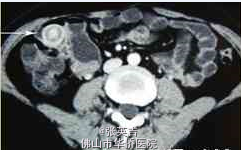

患者生命体征平稳,营养良好。心肺(-),腹软,脐右深压痛,无反跳痛、肌紧张,肠鸣音亢进,未及包块。 妇科B超检查提示:子宫双附件未见明显异常。 全消化道造影提示:远段回肠占位病变(图1)。 腹部盆腔增强CT及小肠重建检查提示:在右下腹,肠腔内有占位,考虑息肉致肠套叠的可能性大,局部系膜血管影增多,周围有大量渗出影及小淋巴结(图2、3)。